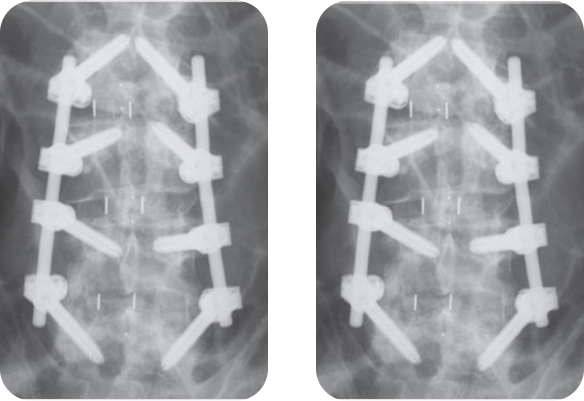

Женщина, 59 лет, дегенеративная нестабильность и стеноз позвоночного канала в сегментах L3-L4 и L4-L5. Установлена транспедикулярная система TangoRS L3-L5 и выполнен межтеловой спондилодез кейджами Pezo-T в сегменте L3-L4 и Pezo-P в сегменте L4-L5.